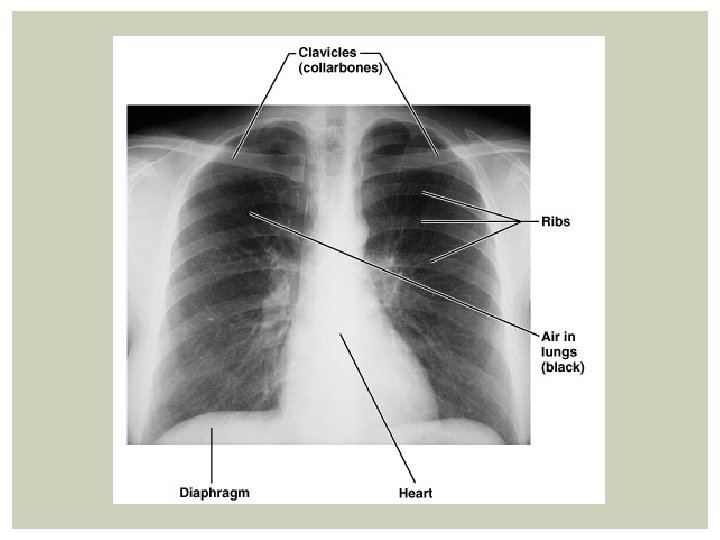

X-ray § Electromagnetic rays; denser tissues block more and are whiter (photographicall y they’re negatives)